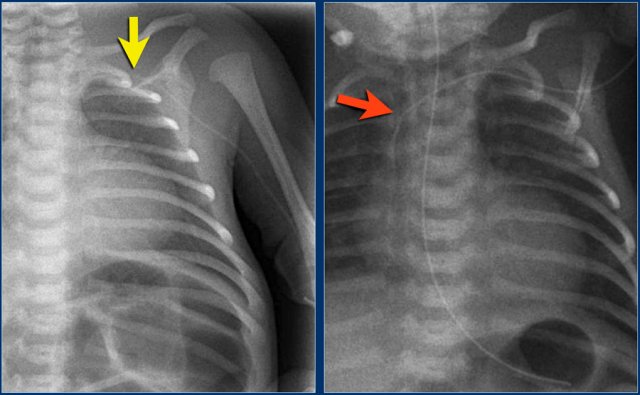

1. Umbilical vein line positioned in the periphery of the liver through the right portal vein.

2. Artery line in the left subclavian artery.